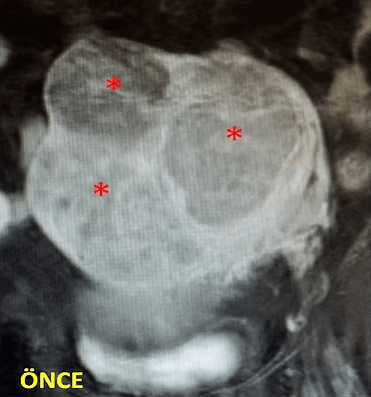

44 yaşında, kabızlık, gaz, sık idrara çıkma şikayetleri mevcut. Emar’da idrar kesesine bası yapan 3 miyom (*) izleniyor ve tek çare olarak histerektomi öneriliyor. Embolizasyondan sonra miyomların öldüğü ve küçüldüğü izleniyor. İşlemden 6 ay sonra hasta şikayetleri tama yakın azalmıştır.